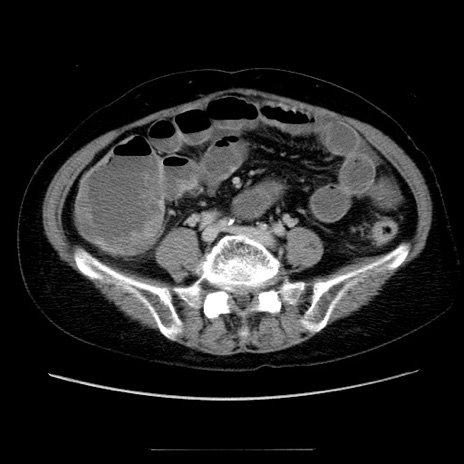

冠状断像

【症例】70歳代女性

【主訴】お腹が張る

【現病歴】1週間くらい前から腹部膨満の自覚あり。昨日夜から増悪したため、本日救急外来受診。

【身体所見】意識清明、BT 36.5℃、BP 165/106mmHg、HR 80bpm、SpO2 98%、腹部:膨満、軟、自発痛・圧痛なし、触診にて不快感あり、腸蠕動音:減弱

【データ】WBC 12600、CRP 1.04